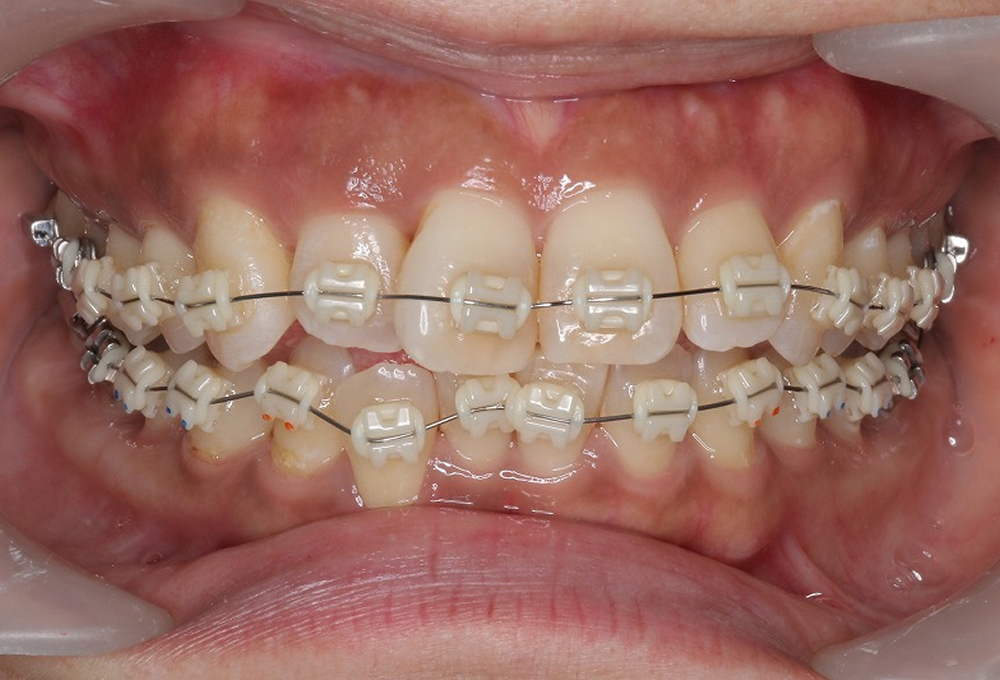

②マルチブラケットにて矯正